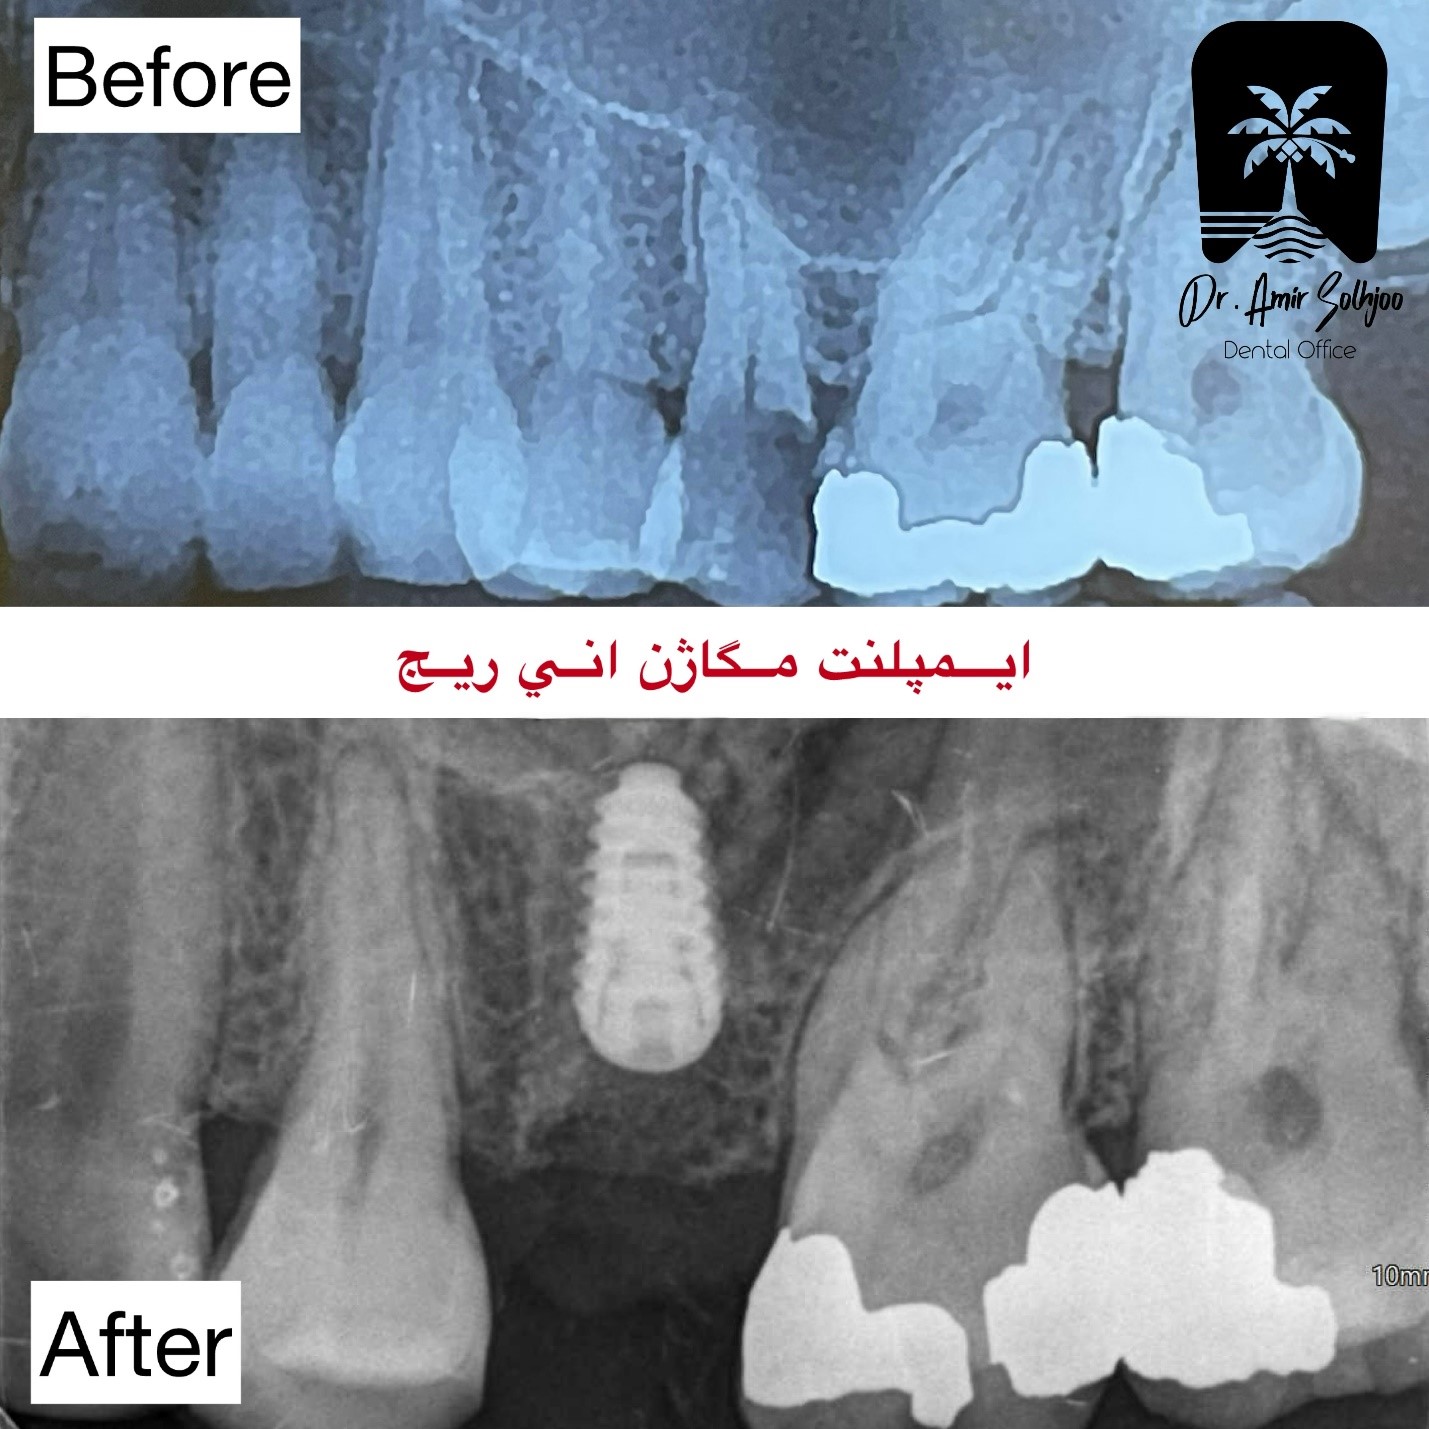

ایمپلنت مگاژن انی ریج

ایمپلنت مگاژن انی ریج به عنوان یک لاین جداگانه و پیشرفته از شرکت مگاژن کره جنوبی، نمایانگر اوج مهندسی و نوآوری در ایمپلنتولوژی مدرن است. این سیستم که به عنوان بهترین ایمپلنت کره‌ای موجود در بازار ایران شناخته می‌شود، نه تنها یک محصول، بلکه یک فلسفه درمانی کامل برای دستیابی به بالاترین سطح ثبات اولیه و زیبایی است. ایمپلنت مگاژن انی ریج با طراحی خاص خود، چالش‌های رایج در استخوان‌های با تراکم پایین و نواحی زیبایی‌حساس را به طور مؤثر حل می‌کند و استانداردهای جدیدی را برای موفقیت بلندمدت تعریف می‌نماید. This article provides an in-depth analysis of the unique features of this system, its mechanism of action and comparative comparison with other top options on the market.

The main philosophy of the AnyRidge magazine implant is based on creating maximum surface contact and mechanical engagement with the existing bone, regardless of its initial quality. This system is specifically designed to overcome the limitations of soft bones (type D3 and D4) that are common in the posterior regions of the jaw. Unlike conventional implants that may create an urgent need for bone grafting in such situations, the Maggen Annie Ridge implant minimizes this need by providing excellent initial stability. مطالعه‌ای در ژورنال معتبر Clinical Implant Dentistry and Related Research بر اهمیت طراحی رزوه و سطح ایمپلنت در دستیابی به ثبات اولیه کافی، به‌ویژه در استخوان‌های با تراکم کم تأکید کرده و نشان می‌دهد که طراحی‌های پیشرفته می‌توانند نتیجه‌گیری بالینی را بهبود بخشند (منبع).